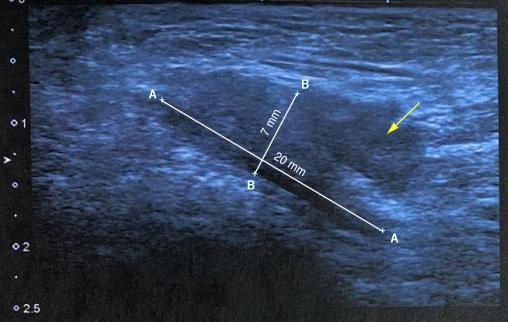

Le diagnostic est essentiellement clinique mais des examens d’imagerie peuvent être réalisés : échographie (figure)ou IRM, en cas de manifestations peu évocatrices.